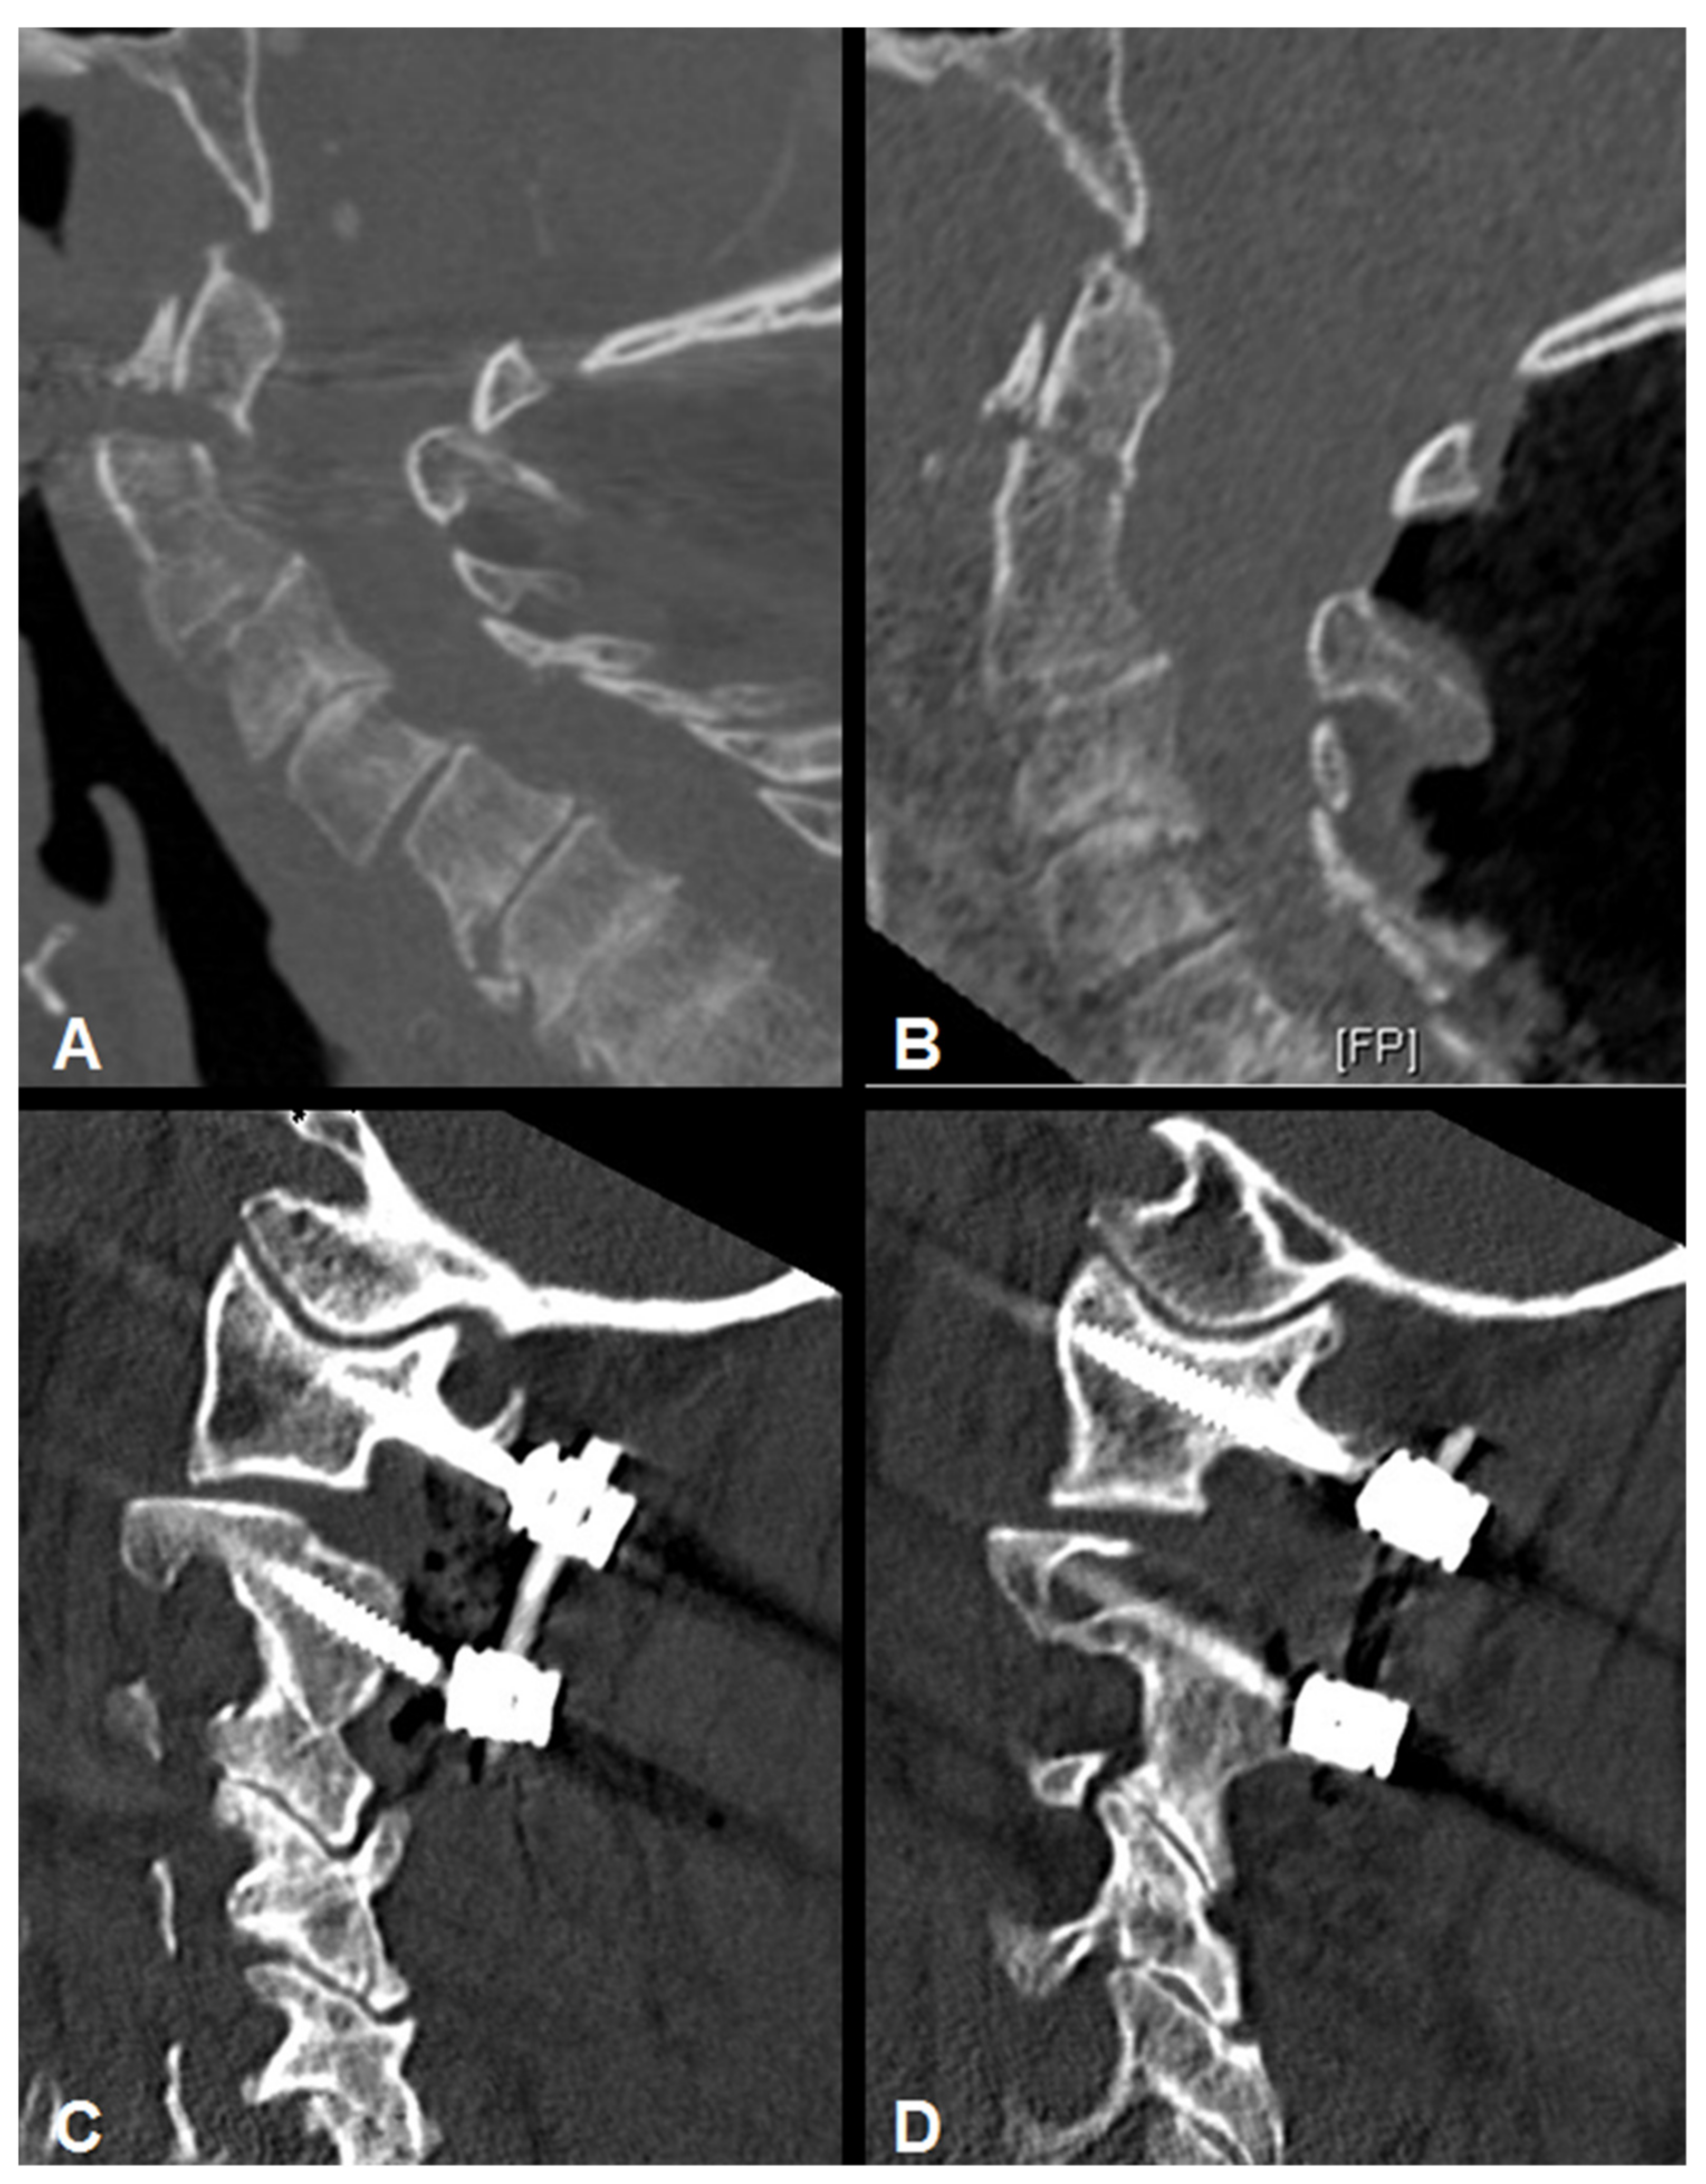

3.4. Radiographic Results

3.5. Complications and Perioperative Course